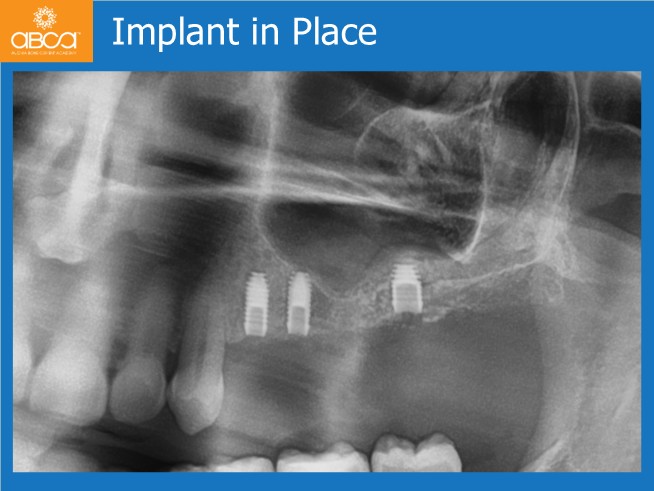

The surgical treatment proceeded successfully in two stages. First, the clinician placed implants in the premolar sites and performed the sinus lift. After six months, an implant was placed in site #27 (15).

Finally, a fixed bridge restored all edentulous areas, achieving an excellent postoperative outcome and high patient satisfaction.